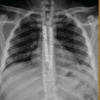

Over the course of 2 years, 80 patients presented with patella fractures at our center, out of which 12 patients had comminuted patella fractures. Informed consent was obtained from 12 patients and who were included in the study. Out of 12 patients, One was female and 11 were male. The average age was found to be 42 years. The average time of follow-up was 1.2 years. Out of 12 patients, all 12 (100%) achieved union. One patient (8%) had anterior knee pain and difficulty while kneeling due to implant impingement. No elective implant removal was done. One patient (25/Male) had suffered a transverse patella fracture, which was fixed using standard tension band wiring, following which he again suffered a fall to the same knee 2 weeks postoperatively, which had resulted in failure of tension band wiring and comminution of the fracture fragments (Fig. 5a and b). The tension band wiring was removed, the fracture was reduced and fixed using a star-shaped patella plate, which had gone onto the united well (Fig. 5g-l), and achieved knee flexion of 130° without any extensor lag at 1-year follow-up (Fig. 6).